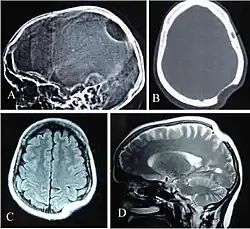

.jpg)

Microglia are the tissue-resident phagocytes of the central nervous system. CSF1R signaling promotes migration of primitive microglia precursor cells from the embryonic yolk sac to the developing brain prior to formation of the blood-brain-barrier. In perinatal development, microglia are instrumental in synaptic pruning, a process in which microglia phagocytose weak and inactive synapses via binding of microglial complement receptor 3 (CR3) (complex of CD11b and CD18) to synapse-bound iC3b. Csf1r loss-of-function inhibits synaptic pruning and leads to excessive non-functional synapses in the brain. In adulthood, CSF1R is required for the proliferation and survival of microglia.[12] Inhibition of CSF1R signaling in adulthood causes near-complete (>99%) depletion (death) of brain microglia, however reversal of CSF1R inhibition stimulates remaining microglia to proliferate and repopulate microglia-free niches in the brain.[13] Production of CSF1R ligands CSF-1 and IL-34 is increased in the brain following injury or viral infection, which directs microglia to proliferate and execute immune responses.[12]